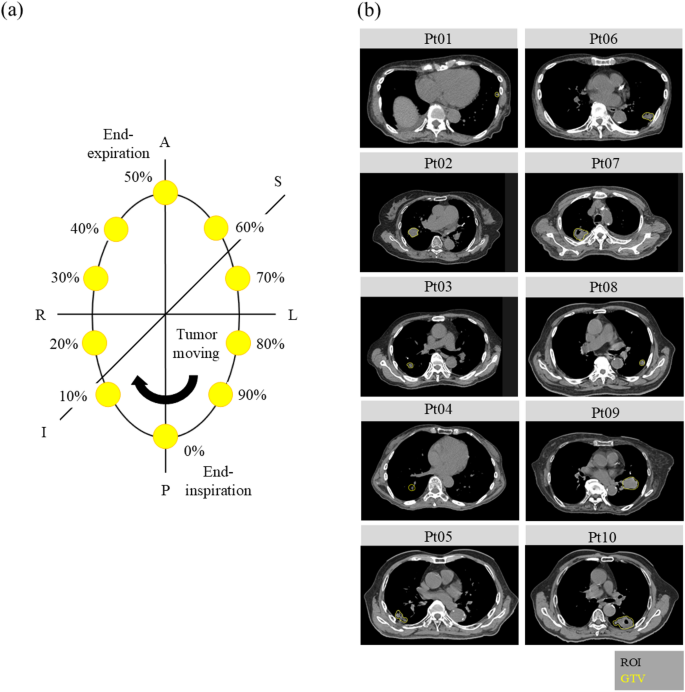

Ten patients with clinically diagnosed stage IA NSCLC (cT1N0M0 per UICC 9th Edition) between March 2021 and September 2023 who underwent planning 4D-CT scanning were included in this study. Patients were deemed medically inoperable by multidisciplinary evaluation or operable but elected SBRT after declining surgery. The median age was 81 years (range, 64–95); six were male and four were female. This study was approved by the Institutional Review Board of Tokushukai Group Ethics Committee (No.2291/September 19, 2023). All methods were performed in accordance with the relevant guidelines and regulations. The review board of Tokushukai Group Ethics Committee waived the need for informed consent by offering an opt-out option on the institution’s homepage due to its retrospective nature (Tokushukai Group Ethics Committee, https://www.mirai-iryo.com/service/index.php#s03). CT was performed using a 20-row scanner (SOMATOM Definition AS Open; Siemens AG, Munich, Germany). Each 4D-CT image was reconstructed into ten phases (0–90%), with 0% and 50% representing the end-inspiration and end-expiration phases, respectively (Fig. 4a), using a respiratory management system (ANZAI belt; Anzai Medical Co., Ltd., Tokyo, Japan). The reconstruction resolution was 0.98 × 0.98 × 2 mm. Experienced radiation oncologists contoured the GTVs on the 4D-CT images across all breathing phases in the RayStation Treatment Planning System owned by our institution (version 10A; RaySearch Laboratories, Stockholm, Sweden). The RayStation was installed on a local Windows workstation with an Intel Xeon CPU and NVIDIA RTX A5000 GPU. Relevant OARs, including the lungs, spinal cord, heart, and esophagus, were delineated on the end-expiration phase CT, which served as the reference CT. A deformable image registration employing an anatomically constrained deformation algorithm was applied between the reference phase CT (end-expiration, 0%) and the 4D-CTs of other phases. Consequently, all OARs on the reference CT were expanded to the other phases, and the radiation oncologists modified the contouring if needed. Table 4 summarizes the locations, volumes, and motion amplitudes of the tumors in enrolled patients. Figure 4b shows the tumor volumes and locations in the axial plane for the ten patients.

Schematic view of respiratory phase and representative CT images. (a) Correspondence diagram for the respiration phase of 4D-CT. (b) Axial plane image of the maximum exhale phase in 4D-CT for 10 patients, showing lung tumors (gross tumor volume) delineated in yellow. GTV, gross tumor volume; ROI, region of interest.